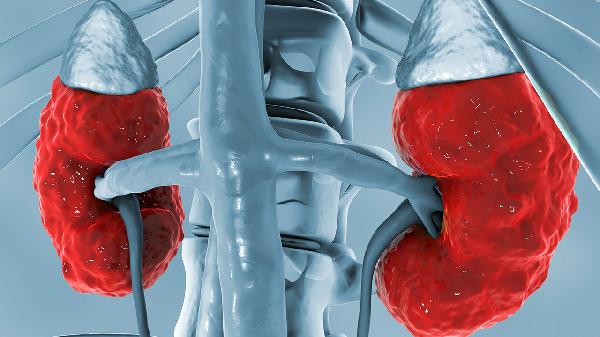

隐匿肾炎患者的寿命与疾病控制情况密切相关,积极治疗和管理可以显著延长生存期。隐匿肾炎是一种慢性肾脏疾病,早期症状不明显,但如果不及时干预,可能进展为慢性肾功能衰竭。治疗方式包括药物治疗、饮食管理和生活方式调整,同时定期监测肾功能指标是关键。